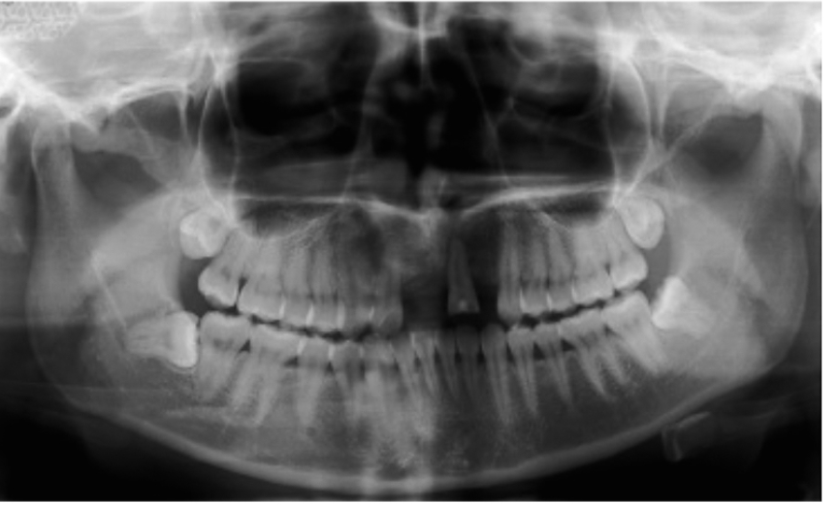

图1 术前全景片显示A1B2缺失

首先在进行临床检查时,可以观察到缺牙区的宽度和厚度,用手指扪诊时前庭沟骨质没有明显的凹陷,这种情况可以拍摄牙片了解牙槽骨状况及与鼻腔的距离。由于牙片显示的范围有限,最好能够拍摄全景片了解邻近结构的情况,比如邻牙的情况、鼻腔底的距离,切牙孔的大小与位置等等。